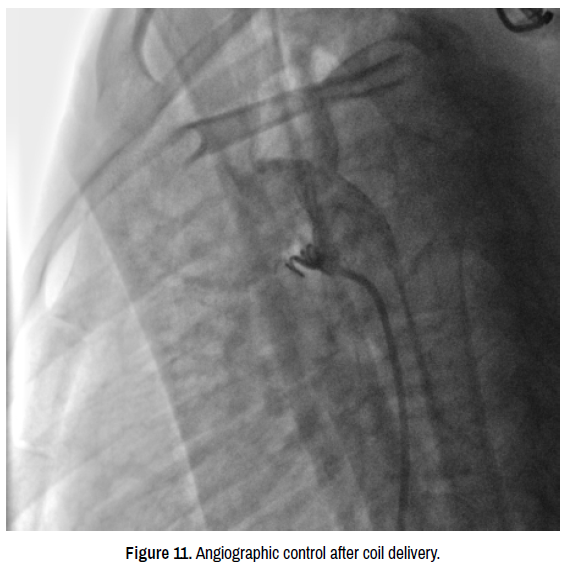

vasculitis-coil-delivery

Figure 11. Angiographic control after coil delivery.

Technique: We started the procedure by sedating the child under Sevoflutane with a mask and monitoring the heart rate, blood pressure and oxygen saturation. Then we proceeded to rigorous disinfection and establishment of sterile fields and punctured the right femoral artery under local anesthesia with Lidocaine 1% using 5F radial sheath then we injected Heparin at dose of 100 units per Kg (1700 units). We then introduced a JR 3.5 5F diagnostic catheter on a 0.035’’ wire to the aortic isthmus and then we opacified the channel by manual injections of ULTRAVIST 300 contrast to confirm its diameter by angiographic measurement in profile view (1.3 +/- 0.3 mm) (Figure 9). Then we took a JR 4 5F guiding catheter closed by an angioplasty Pyton, we crossed the channel to the pulmonary artery by a 0.014’’ hydrophilic wire and a 0.035’’ straight wire used as a body wire to partially engage the PDA The PDA being long with 1.6 mm in diameter, we opted for a coil of 5/5 (5 loops of 5mm) deployed erect in the pulmonary artery after pulling back the guiding catheter, then the central mandrel of the coil is gradually removed to deploy 1.5 loops in the pulmonary artery, 1.5 loops in the channel and 2 loops in the aorta (Figure 10). An echocardiographic control is carried out at this time to confirm the right coil positioning, the channel closure and the absence of arterial clutter on both aorta and PA (V max < 2m/s). We ended up with an angiographic control with contast injection before delivering the coil by the counter-clockwise rotation of the external part of its delivery system (Figure 11). A final angiographic and ultrasound control was carried out 10 minutes later in Cath Lab before the removal of the material and manual compression of the right femoral artery. The procedure skin to skin took 30 minutes. A compressive bandage was placed for 12 hours. The child was monitored in the awakening room for 2 hours at the end of which she returned to the normal hospital bed.